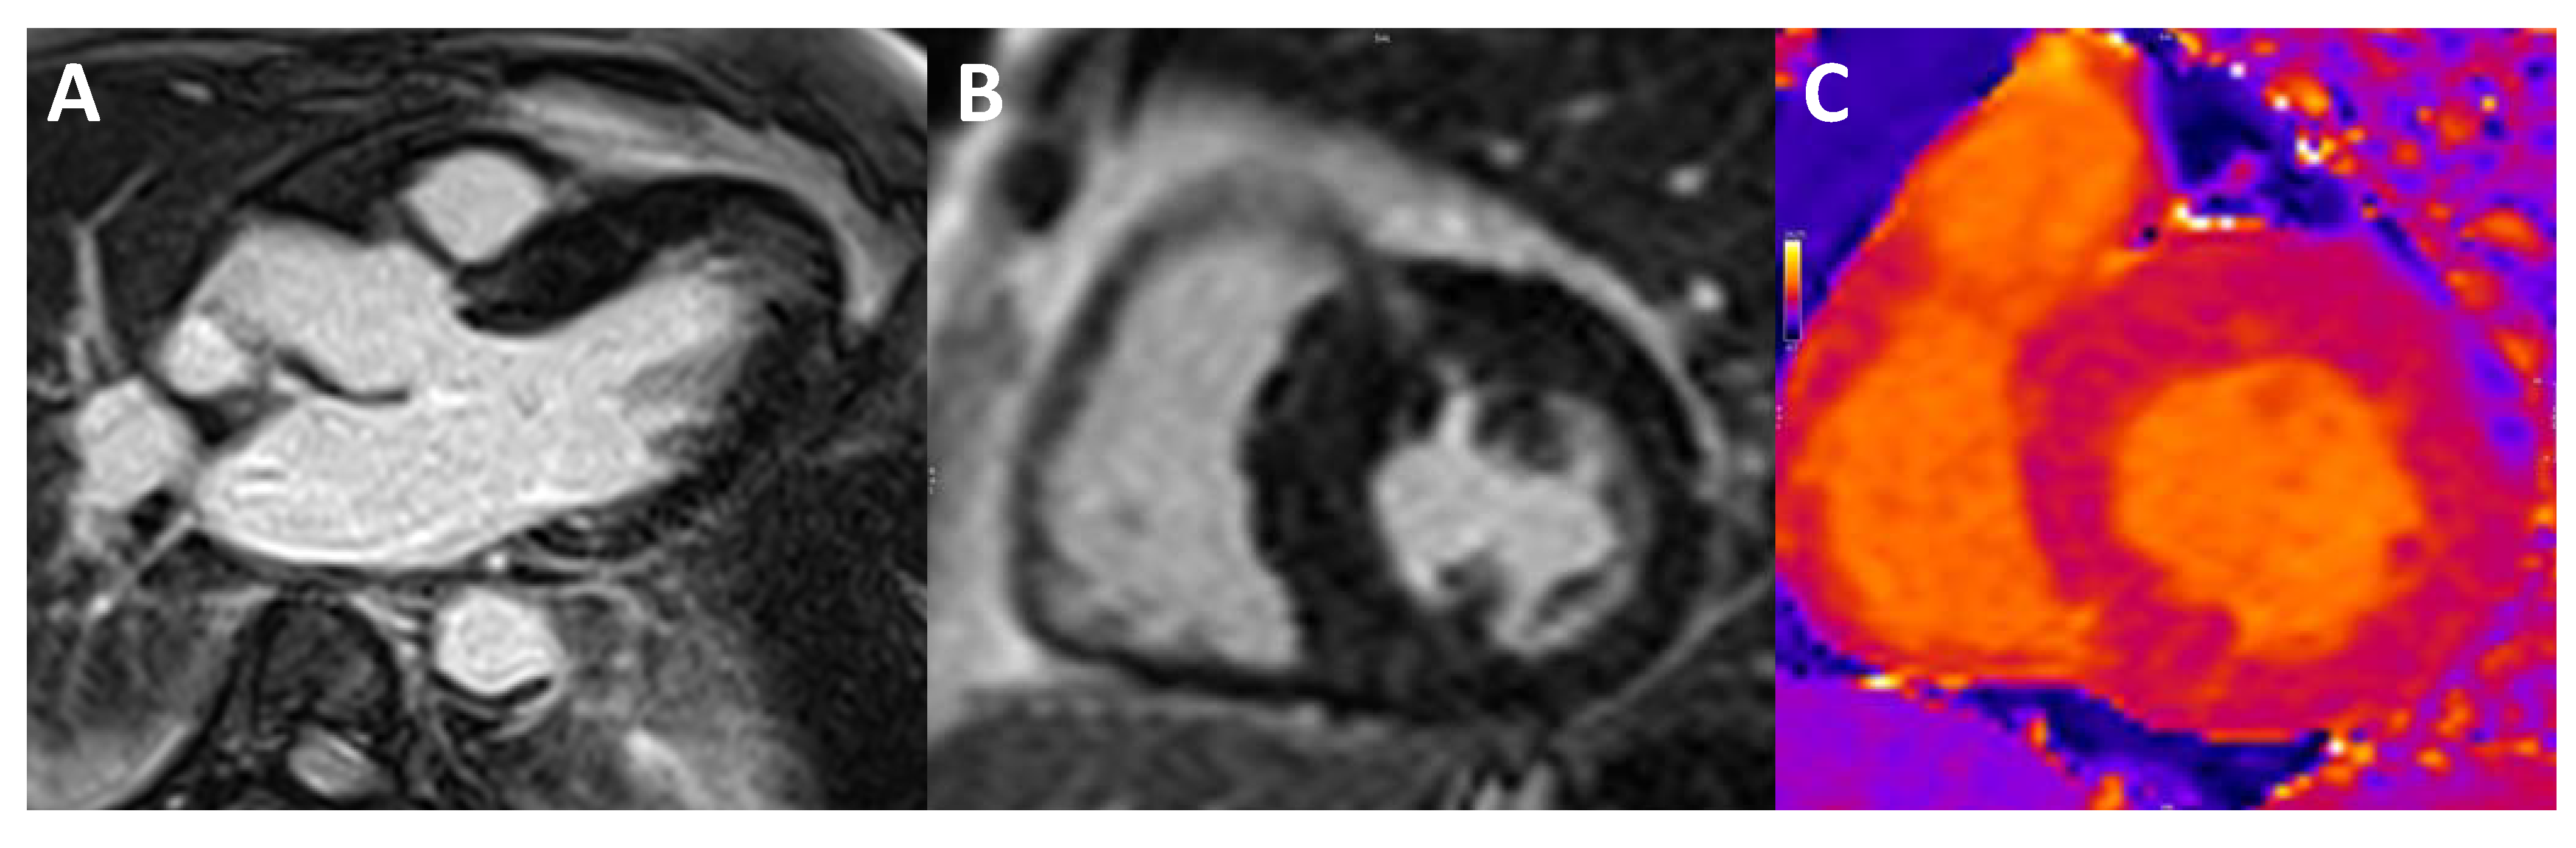

6. Left Ventricular Noncompaction